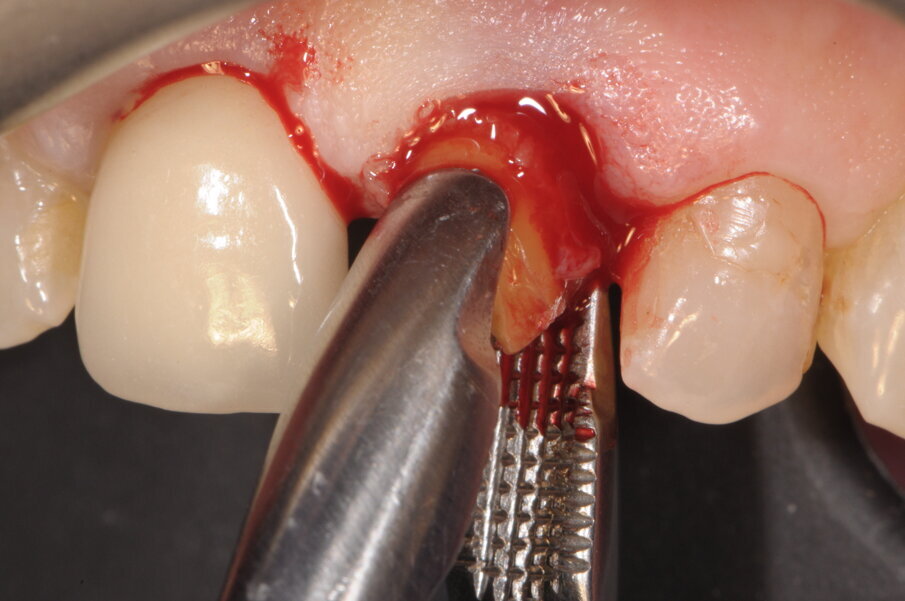

In paziente di sesso femminile ASA1, non fumatrice con ricostruzione endo-protesica su 1.1 e 2.1 si evidenzia un’irrimediabile frattura verticale di 2.1 con perdita di una estesa porzione coronale (Fig. 1), confermata dalla radiografia endorale eseguita con centratore (Fig. 2). Al sondaggio non si percepisce perdita ossea a livello circonferenziale. Nella stessa seduta si procede ad avulsione radicolare cercando di non lesionare la struttura ossea e conservando anche le limitrofe papille. Data la richiesta di estetica manifestata dalla paziente e il miglioramento di entrambe le corone cliniche si procede con l’inserimento di un’impianto endosseo secondo la tecnica postestrattiva immediata e contestuale posizionamento di provvisorio con l’unione di entrambe le corone protesiche.

Fig. 1 - Visione al momento della prima visita in cui la paziente aveva fratturato la radice in senso verticale smarrendo la corona.

Fig. 3 - Estrazione della radice eseguita con particolare attenzione al ridotto traumatismo del tessuto osseo e mucoso circostante.